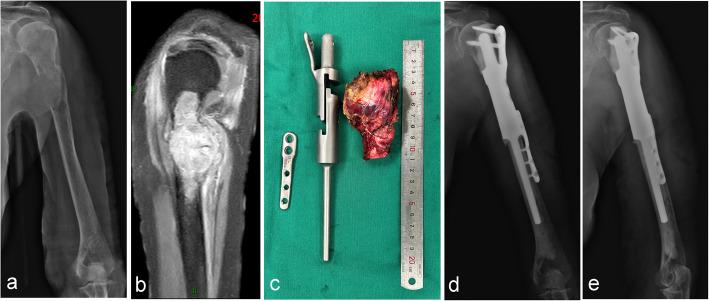

A retrospective analysis of 25 patients treated at two centers with wide resection for primary or metastatic bone tumors (femur, tibia, humerus) followed by reconstruction using ultra-short stem intercalary prostheses combined extracortical plates. Clinical outcomes were assessed using the Visual Analogue Scale (VAS) and Musculoskeletal Tumor Society (MSTS) score. Survival rates were calculated using the Kaplan-Meier method, and complications were classified according to the Henderson system.

The mean follow-up was 20.2 months (range, 3-101 months). The average length of the ultra-short stems was 41.3 ± 9.6 mm. Mean operative time was 164 ± 61.3 min, blood loss averaged 646.4 ± 375.5 ml and the mean defect size was 122 ± 52.1 mm. Postoperative VAS scores were significantly lower than preoperative levels (P < 0.05). The mean MSTS score was 24.2 ± 3.5 (range, 15-29). Kaplan-Meier analysis revealed prosthesis survival rates at 1, 2, 3, and 5 years of 91.7%, compared to patient survival rates of 74.5%, 52.7%, 52.7%, and 52.7%. Postoperative complications occurred in 12% of patients (3/25), including one case of aseptic loosening (ASL), and two patients required reoperation.

Ultra-short stem intercalary prostheses with extracortical plates provide a viable, effective option for reconstruction of short bone stumps after tumor resection, offering improved functional outcomes and acceptable prosthesis failure rates.